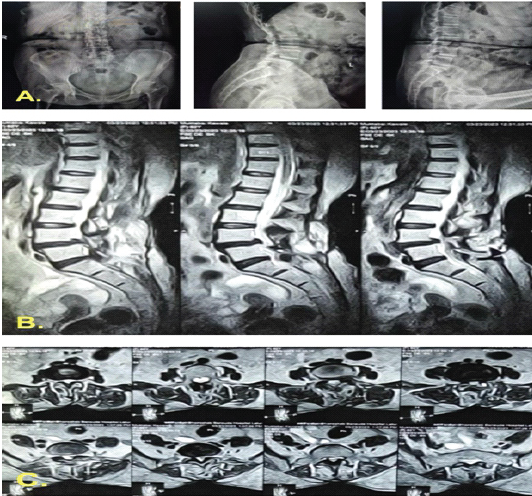

A 65-year-old woman with hypertension, diabetes mellitus (hemoglobin A1c [glycated hemoglobin] 6.8), ischemic heart disease, and a history of L4–L5 lumbar decompression in 2018 presented with chronic low back pain, neurogenic claudication, and urinary urge incontinence. Imaging revealed L4–L5 grade I post-laminectomy spondylolisthesis with spinal stenosis (Fig. 1).

Figure 1: Pre-operative imaging of L4–L5 grade I spondylolisthesis with spinal canal stenosis. (a) Standing anteroposterior and lateral radiographs at presentation demonstrating L4–L5 spondylolisthesis. (b) T2-weighted sagittal magnetic resonance imaging showing canal stenosis at the L4–L5 level. (c) T2-weighted axial magnetic resonance imaging at the same level illustrating circumferential dural sac compression.